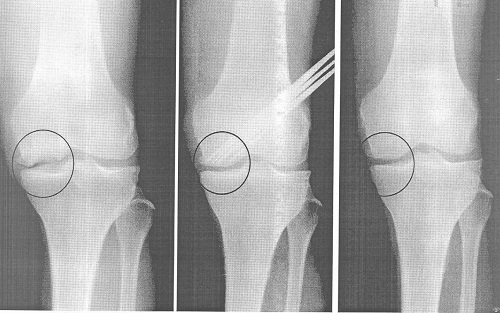

Конечно, в запущенном виде можно визуально определить увеличение, деформацию колена. Но гораздо надежнее работают методы исследования — рентгенография, УЗИ, компьютерная томография, МРТ – магнитно-резонансная томография. Любой из этих способов может показать изменения хрящевой ткани, а тем более – костные наросты вокруг головок сустава.

В тяжелых же случаях, когда функция колена полностью нарушена, оно сильно деформировано, вызывает постоянную боль, врач может принять решение, что необходима операция. Методы оперативного лечения бывают разные – от наложения металлических конструкций, до замены его частей на искусственные. В особо трудных случаях хирург заменит полностью весь сустав.